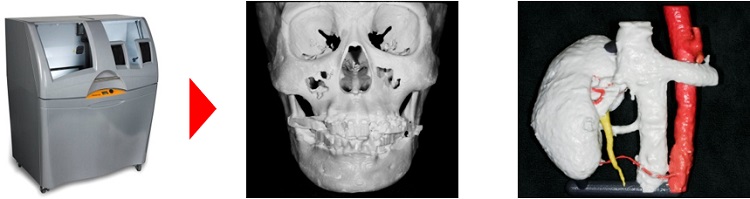

2. Production of three-dimensional structure model for dental field and medical field

We dental technicians of this laboratory offer 3D structure models for not only dentists but also medical doctors. Accurate 3D structures of a diseased site in each patient enable them to select an appropriate therapeutic method, and to do rehearsals for the operation with medical staffs. Thus, effective use of 3D structure models enable doctors to accomplish accurate and safer surgery, and to shorten surgical time.

Process of making 3D models

making model by 3D printer completed 3D model The applications of

the technique to constructed

medical field:kidney 3D model